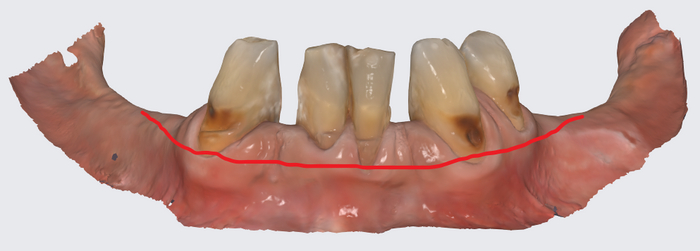

Вот как выглядит цифровая принтованная постановка:

Цифровая принтованная постановка